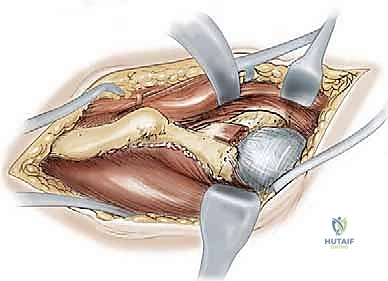

1. النهج الجراحي (The Surgical Approach)

يستخدم الدكتور هطيف شقاً جراحياً تجميلياً يُعرف بـ (Bikini Incision) أو نهج (Smith-Petersen) المعدل. يسمح هذا النهج بالوصول إلى جميع أجزاء الحوض الأمامية والداخلية دون قطع العضلات الرئيسية، بل يتم فصل العضلات وإبعادها بلطف (Muscle-sparing approach)، مما يسرع التعافي بشكل كبير.

2. سلسلة قطع العظام (The 5 Osteotomies)

يكمن سر نجاح جراحة PAO في إجراء خمسة قطوع عظمية منفصلة حول الحُق، لتحريره بالكامل عن باقي الحوض، مع ترك العمود الخلفي سليماً كدعامة أساسية.